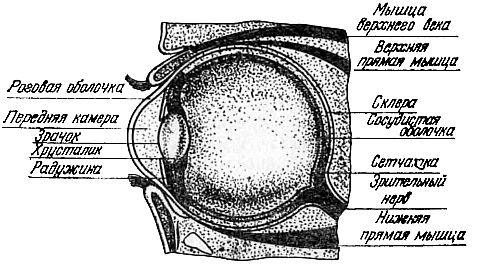

Глаз человека представляет собой почти шарообразное тело, которое покоится в костной черепной полости, открытой с одной стороны. На рис. 1 изображен разрез глазного яблока и показаны основные детали глаза.

Рис. 1. Схематический разрез глаза человека.

Основная часть глазного яблока с внешней стороны ограничена трехслойной оболочкой. Внешняя твердая оболочка называется склерой (по-гречески — твердость) или белковой оболочкой. Она охватывает со всех сторон внутреннее содержание глаза и непрозрачна на всем своем протяжении за исключением передней части. Здесь склера выдается вперед, совершенно прозрачна и носит название роговой оболочки.

К склере примыкает сосудистая оболочка, переполненная кровеносными сосудами. В передней части глаза, там, где склера переходит в роговую оболочку, сосудистая оболочка утолщается, отходит под углом от склеры и направляется к середине передней камеры, образуя поперечную радужную оболочку.

Сетчаткой называется третья, внутренняя оболочка, представляющая собой свето- и цветочувствительный слой.

Светочувствительность сетчатки не на всем ее протяжении одинакова. В части ее, расположенной против зрачка и несколько выше зрительного нерва, она обладает наибольшей чувствительностью, но ближе к зрачку она становится все менее и менее чувствительной и, наконец, сразу обращается в тонкую оболочку, прикрывающую внутреннюю часть радужной оболочки. Сетчатка представляет собой разветвления по дну глаза нервных волокон, которые затем сплетаются между собой и образуют зрительный нерв, который сообщается с головным мозгом человека.

Сразу же за зрачком глаза расположено совершенно прозрачное, эластичное тело, заключенное в особую сумку, прикрепленную к радужной оболочке системой мышечных волокон. Это тело имеет форму собирательной двояковыпуклой линзы и носит название хрусталика. Назначение хрусталика состоит в том, чтобы преломлять световые лучи и давать на сетчатке глаза ясное и отчетливое изображение предметов, находящихся в поле зрения.

Пространство между роговицей и хрусталиком известно под названием передней камеры глаза. Эта камера заполнена студенистой прозрачной жидкостью. Вся внутренность глаза между хрусталиком и глазным нервом заполнена несколько иного рода стекловидным телом. Являясь средой прозрачной и преломляющей, это стекловидное тело в то же время способствует сохранению формы глазного яблока.

Подвижность глаза обеспечивается действием шести мышц, прикрепленных, с одной стороны, к глазному яблоку, а с другой — к глазной орбите.